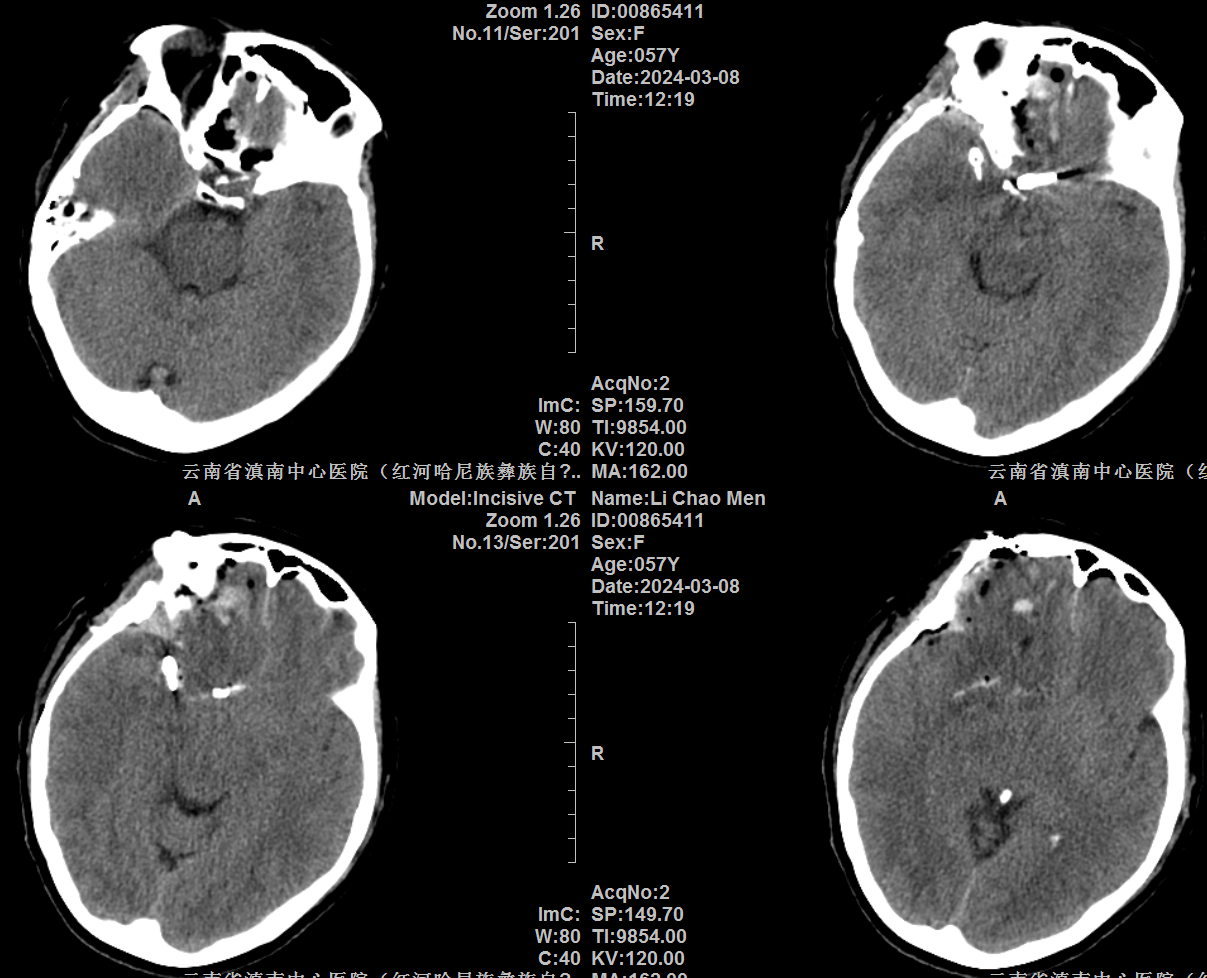

前交通动脉瘤没有理想的夹子,又想保护粘在动脉瘤上的一根静脉,采用头端可调持夹钳,左手把夹子送到位稳住,右手用剥离子调整夹子角度。